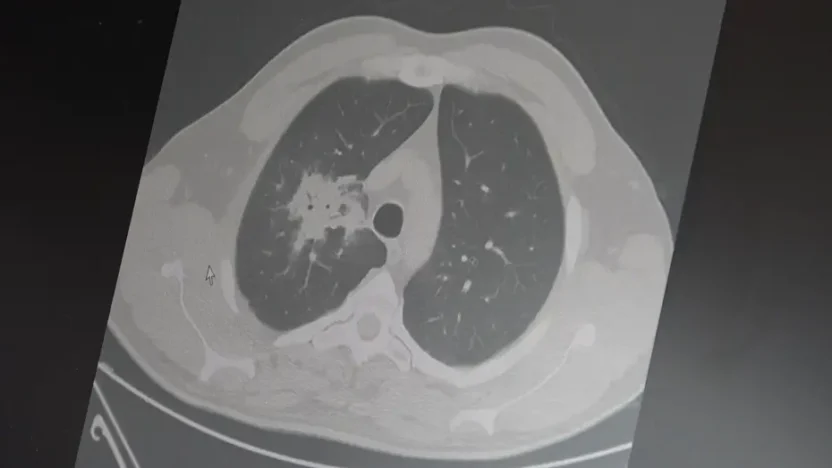

Prof. Dr. Şevket Özkaya, elektronik sigaralarla ilgili beklenen ’20 – 30 yıllık kullanım’ süresinin dolduğunu, 100’den fazla çalışmanın analiz edildiğini ve net olarak kanser riskini artırdığını söyledi.